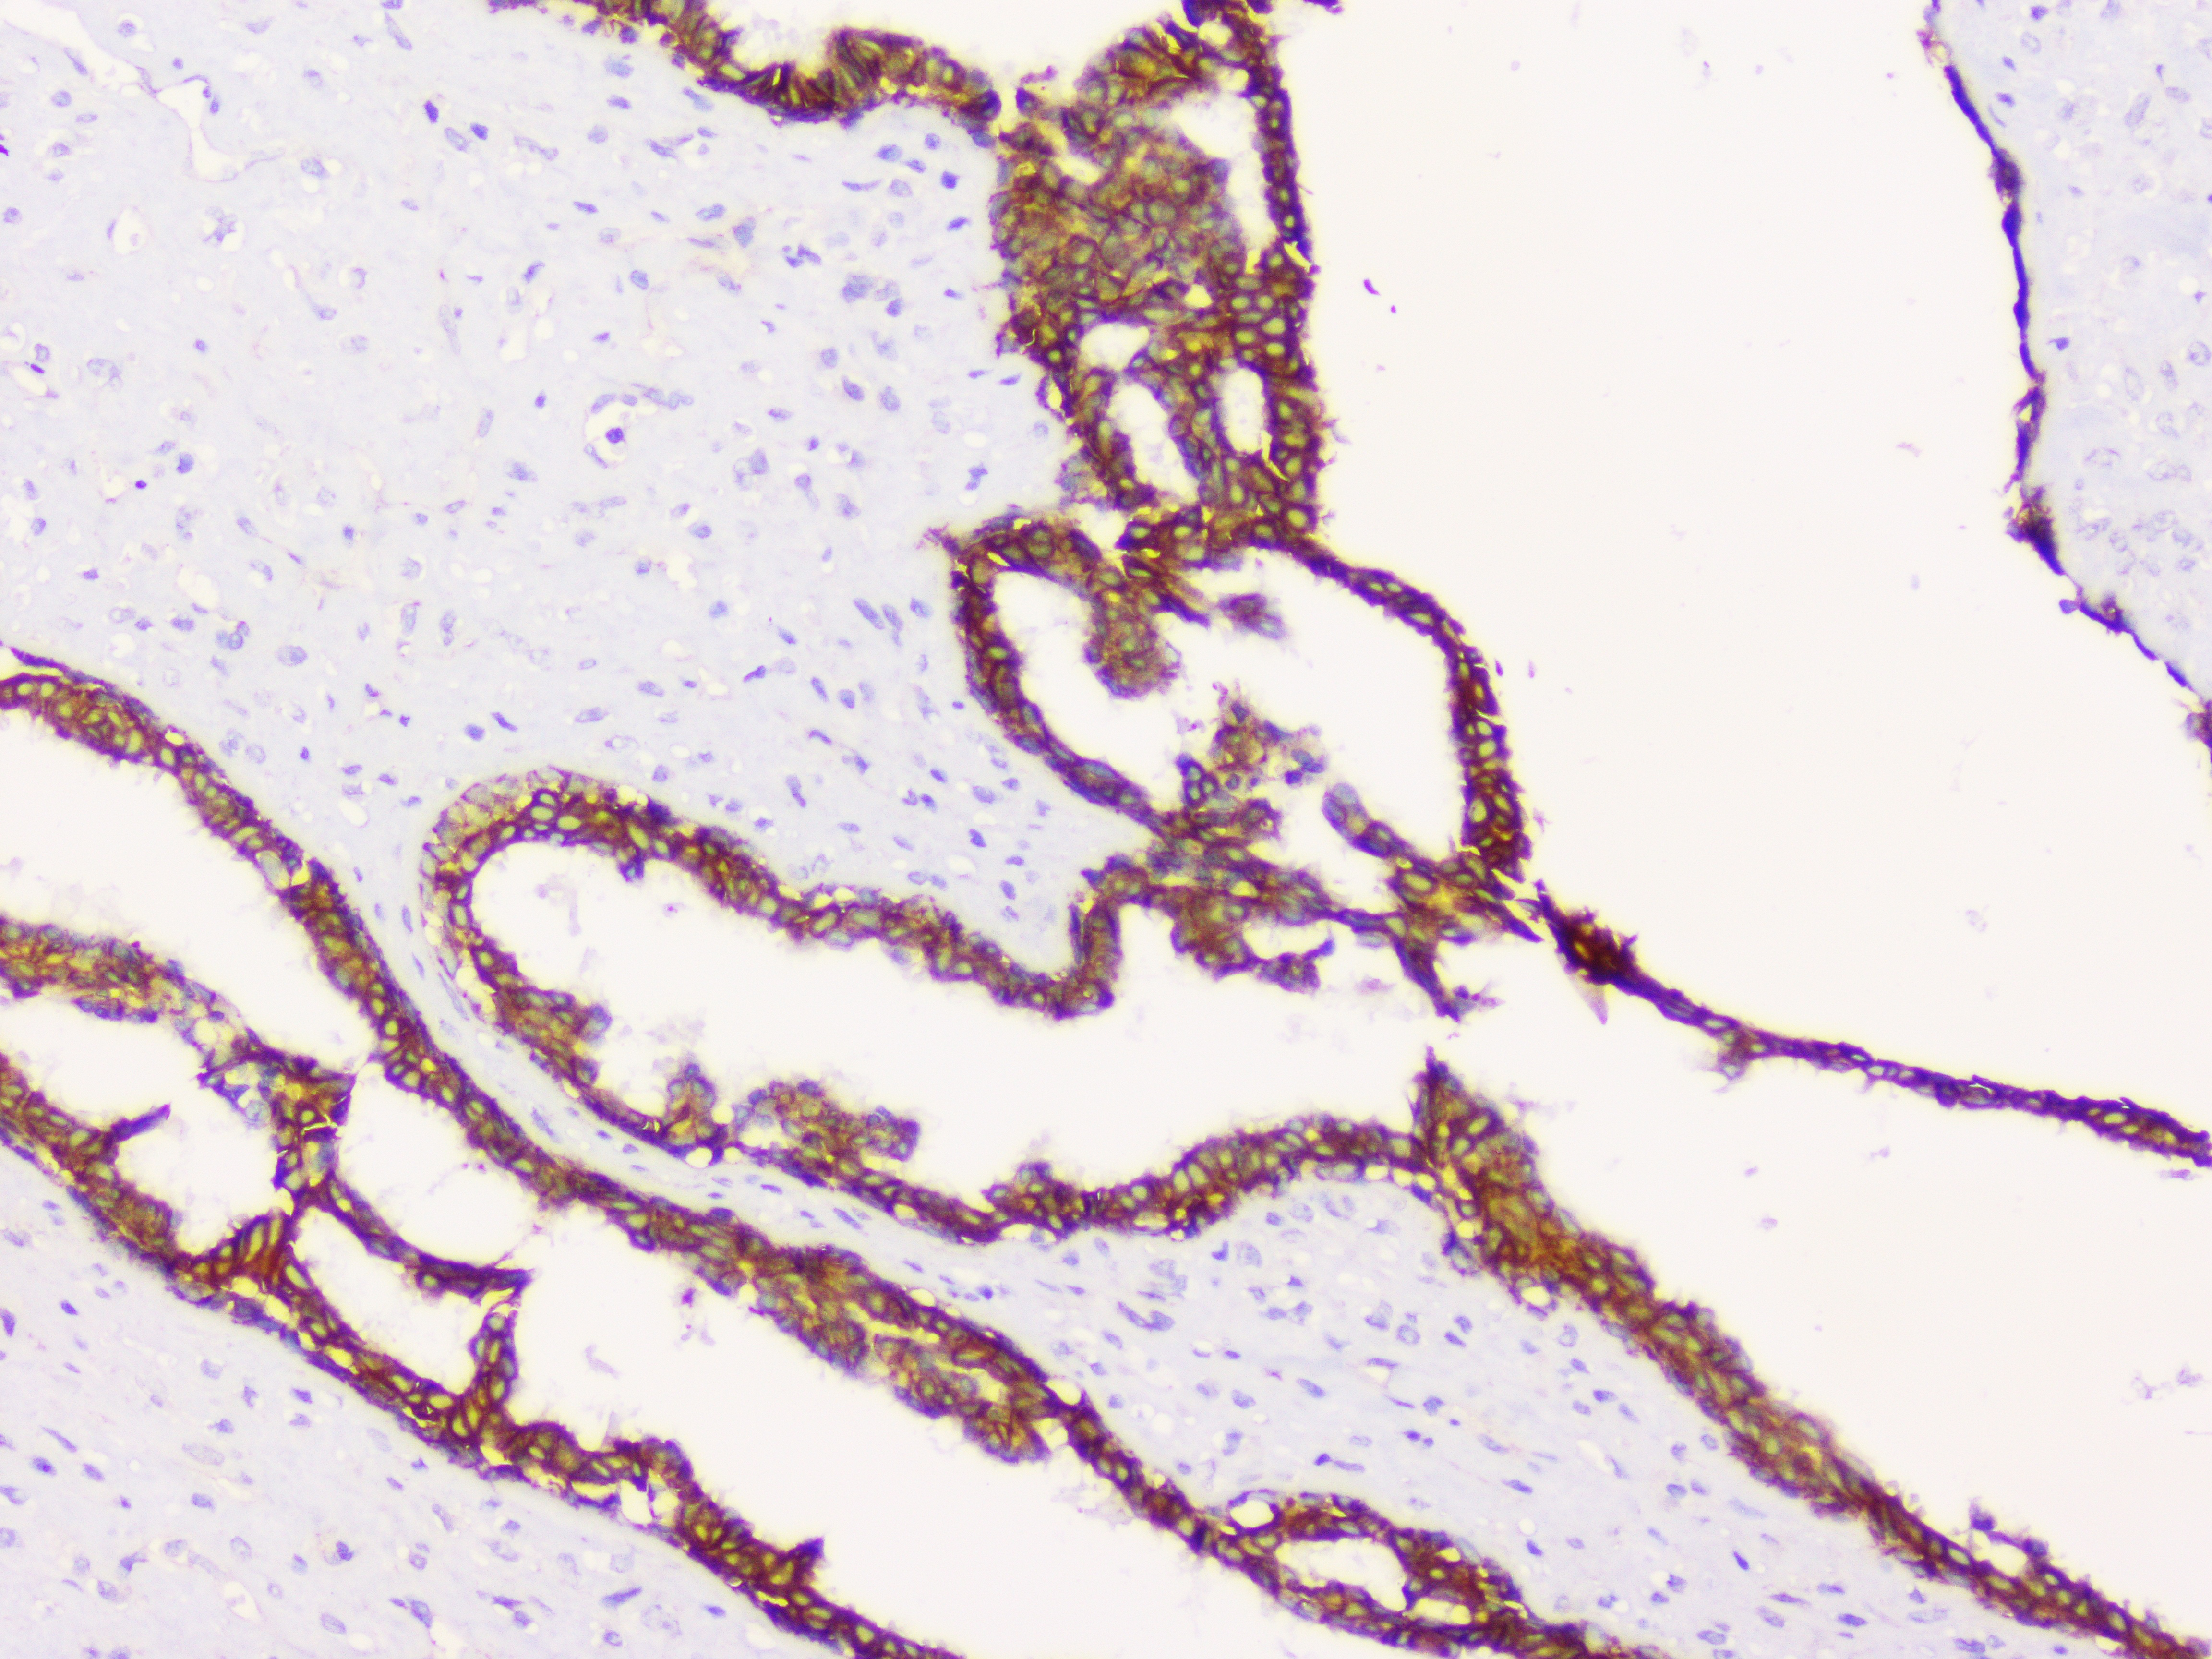

Produktinformationen "Anti-beta Catenin"

Protein function: Key downstream component of the canonical Wnt signaling pathway. In the absence of Wnt, forms a complex with AXIN1, AXIN2, APC, CSNK1A1 and GSK3B that promotes phosphorylation on N-terminal Ser and Thr residues and ubiquitination of CTNNB1 via BTRC and its subsequent degradation by the proteasome. In the presence of Wnt ligand, CTNNB1 is not ubiquitinated and accumulates in the nucleus, where it acts as a coactivator for transcription factors of the TCF/LEF family, leading to activate Wnt responsive genes. Involved in the regulation of cell adhesion, as component of an E- cadherin:catenin adhesion complex. Acts as a negative regulator of centrosome cohesion. Involved in the CDK2/PTPN6/CTNNB1/CEACAM1 pathway of insulin internalization. Blocks anoikis of malignant kidney and intestinal epithelial cells and promotes their anchorage-independent growth by down-regulating DAPK2. Disrupts PML function and PML-NB formation by inhibiting RANBP2-mediated sumoylation of PML (PubMed:17524503, PubMed:18077326, PubMed:18086858, PubMed:18957423, PubMed:21262353, PubMed:22647378, PubMed:22699938, PubMed:22155184). Promotes neurogenesis by maintaining sympathetic neuroblasts within the cell cycle. [The UniProt Consortium]

| Anwendung: | FC, ICC, IF, IHC (paraffin), WB |

| Spezies-Reaktivität: | human, mouse, rat |

| Immunogen: | Recombinant protein corresponding to A2-K233 of Human beta Catenin |